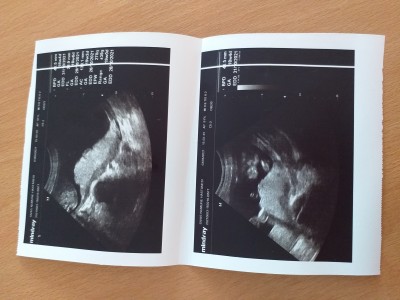

Kızlar bacağı kapalı kordonla birşey gördük dedi ve erkeğe benzetti bugün gittim yine kapalıydı kıza benzetti sizce nedir tahmin yapabilir misiniz anlayanlar baksın.19 haftalığım 1 hafta önce erkek denilmişti.